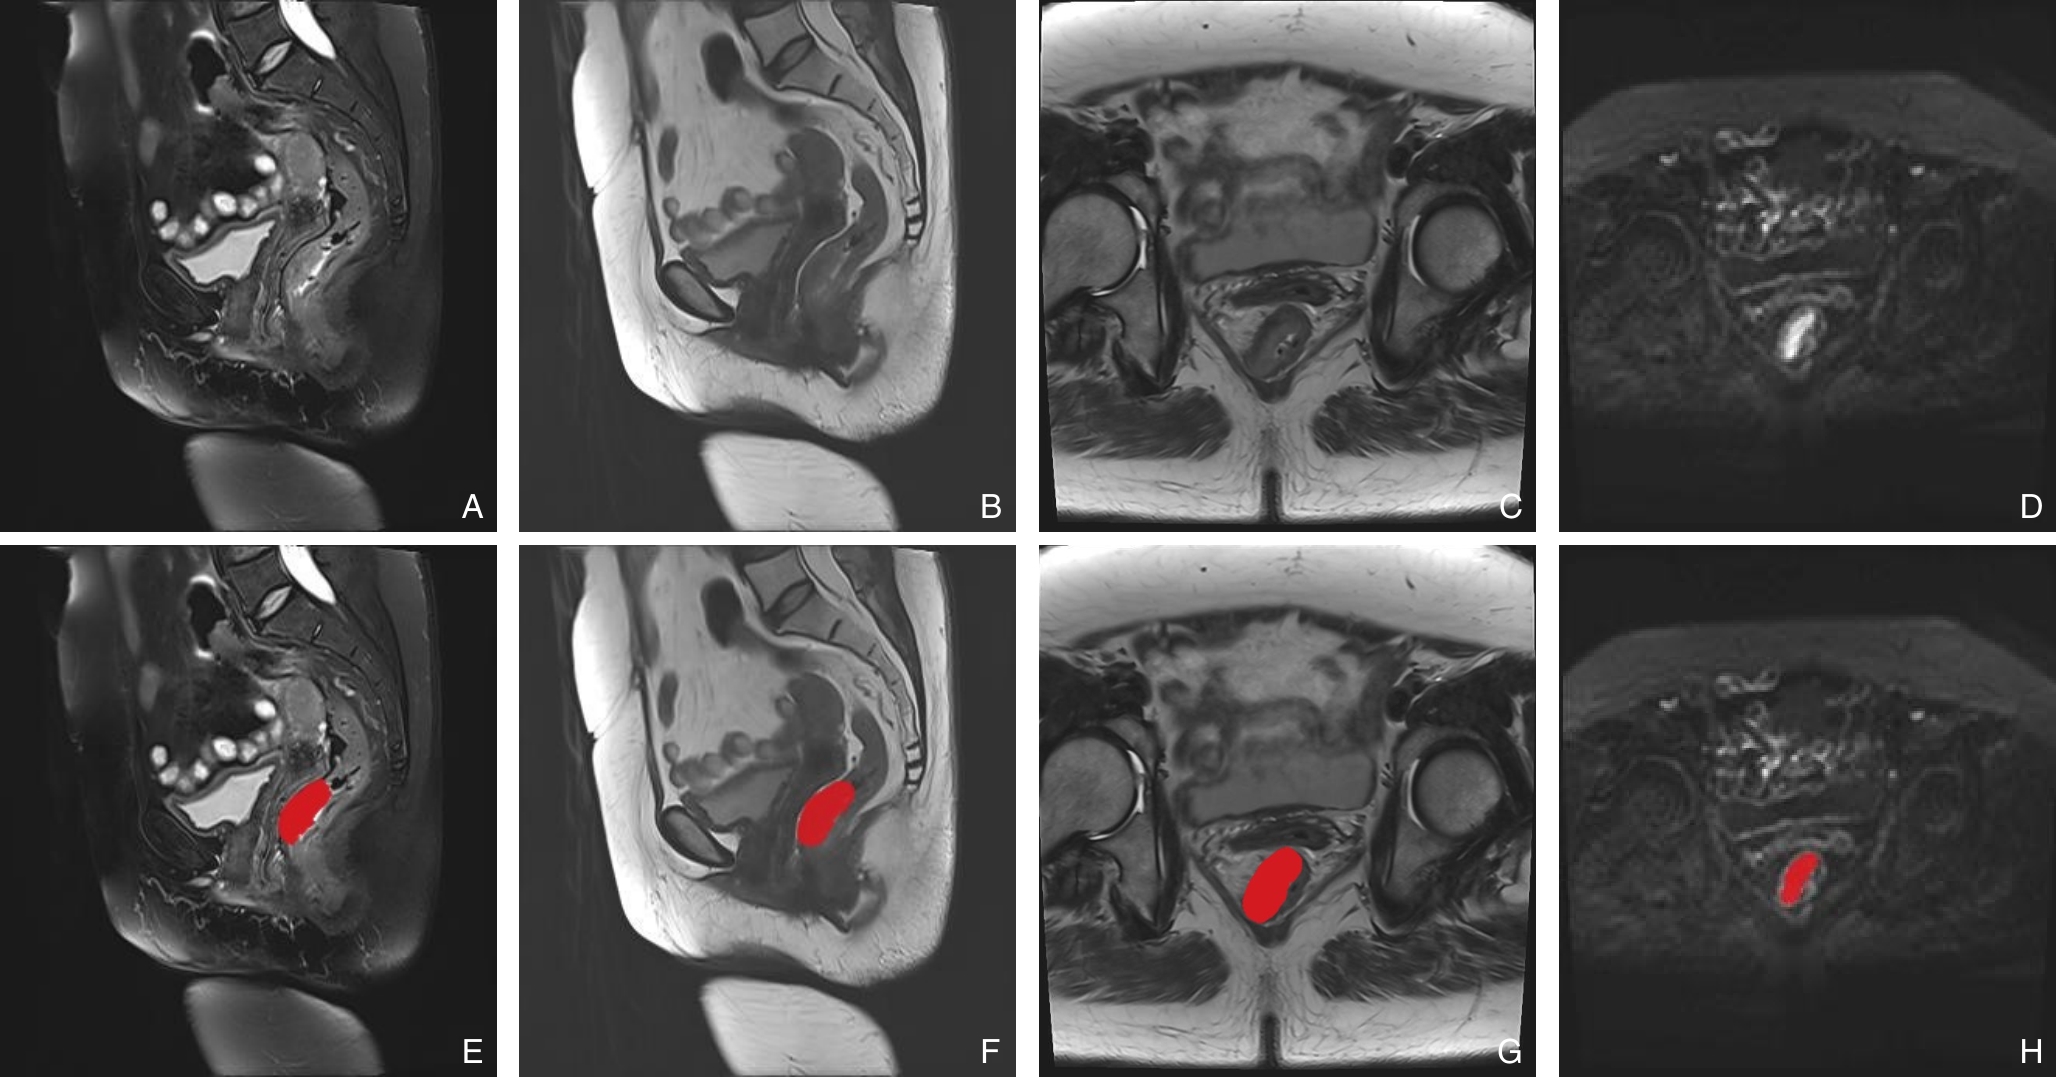

摘要:背景与目的 结直肠癌肝转移(CRCLM)是影响患者预后的主要原因,术前无创、精准诊断对制定治疗方案至关重要。传统临床标志物特异性有限,本研究旨在基于多模态MRI影像组学特征,结合机器学习算法,构建预测CRCLM的高效模型,并评价其临床价值。方法 收集2022年5月—2024年5月于河南省南阳市第一人民医院行术前MRI检查并经病理证实的150例结直肠癌患者,随机分为训练集(n=120)和验证集(n=30)。其中CRCLM 57例,无CRCLM 93例。采用单因素与多因素分析筛选CRCLM独立危险因素,建立临床诊断模型。提取多模态MRI影像组学特征,经LASSO筛选后分别构建Logistic回归(LR)、支持向量机(SVM)、随机森林(RF)模型,并比较其诊断效能。建立临床及影像组学联合诊断模型,并通过受试者操作特征和决策曲线(DCA)评估效能与临床获益。结果 癌胚抗原(OR=1.323,95% CI=1.079~1.567)、糖类抗原19-9(OR=2.512,95% CI=1.225~3.799)及中性粒细胞/淋巴细胞比值(OR=1.881,95% CI=1.354~2.409)是CRCLM独立危险因素(均P<0.05),以上3个因素构建的临床诊断模型曲线下面积(AUC)为0.793。RF模型在训练集与验证集AUC最高(0.770、0.763),优于LR和SVM。基于RF的联合诊断模型在训练集与验证集AUC分别为0.913和0.947,明显优于单独临床或影像组学诊断模型,DCA显示联合诊断模型具有最高临床净获益。结论 RF模型在影像组学预测中表现最佳,其与临床特征结合的联合模型能显著提高CRCLM的无创诊断效能,具备较高的临床应用价值。